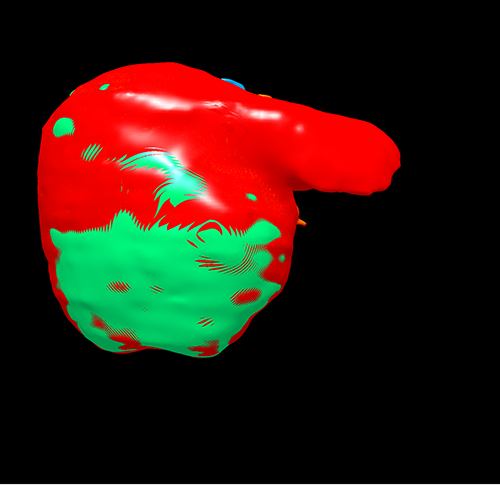

右肝癌---右三肝切除